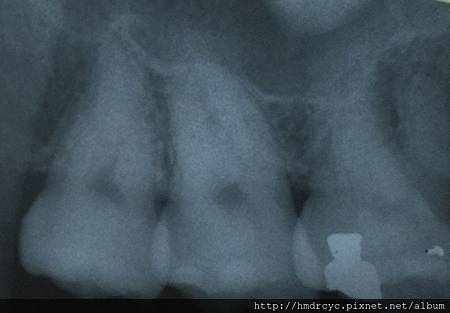

手術前確認X光片預先了解牙齒的位置與角度

全口片可以預先知道牙根型態與相關解剖位置